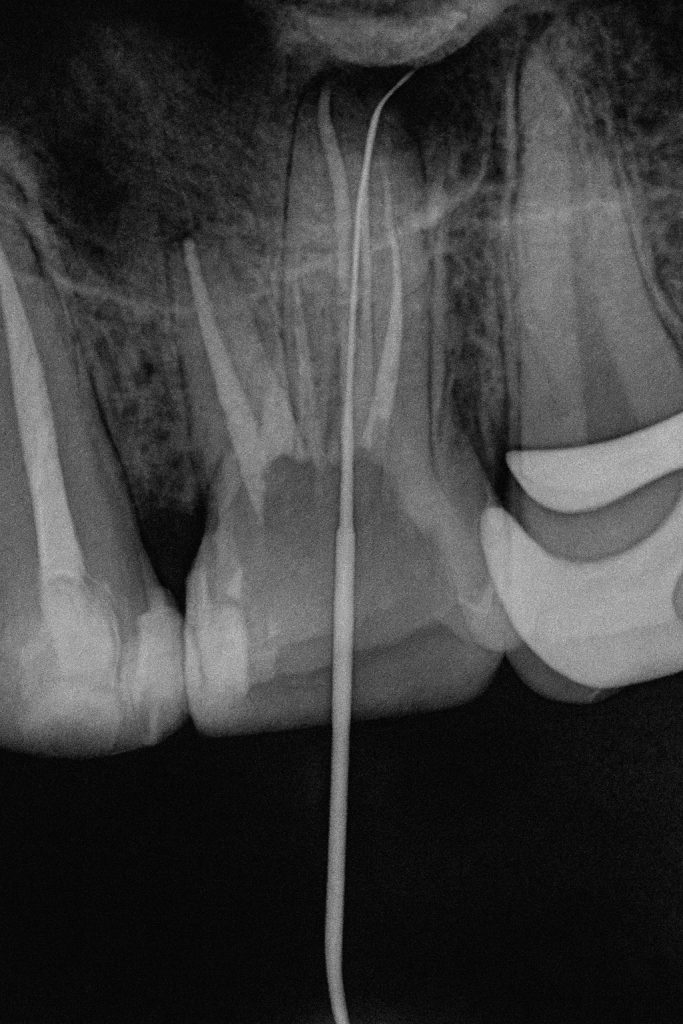

- Using pre-operative CBCT, the palatal root of the first molar was mapped for the suspected split.

- Under magnification, the canal division was identified and negotiated using C+ files and K-files #6–10 with EDTA gel.

- Working length was confirmed with an apex locator and radiographs.

- Rotary NiTi system was used for shaping; irrigants included 5.25 % NaOCl and 17 % EDTA, both sonically activated for effective disinfection. (Fig 3–4)

Obturation was performed using bioceramic sealer with warm vertical compaction, ensuring a dense, continuous fill into the palatal split and accessory canals. Post-operative radiograph confirmed ideal obturation and apical control. (Fig 7)